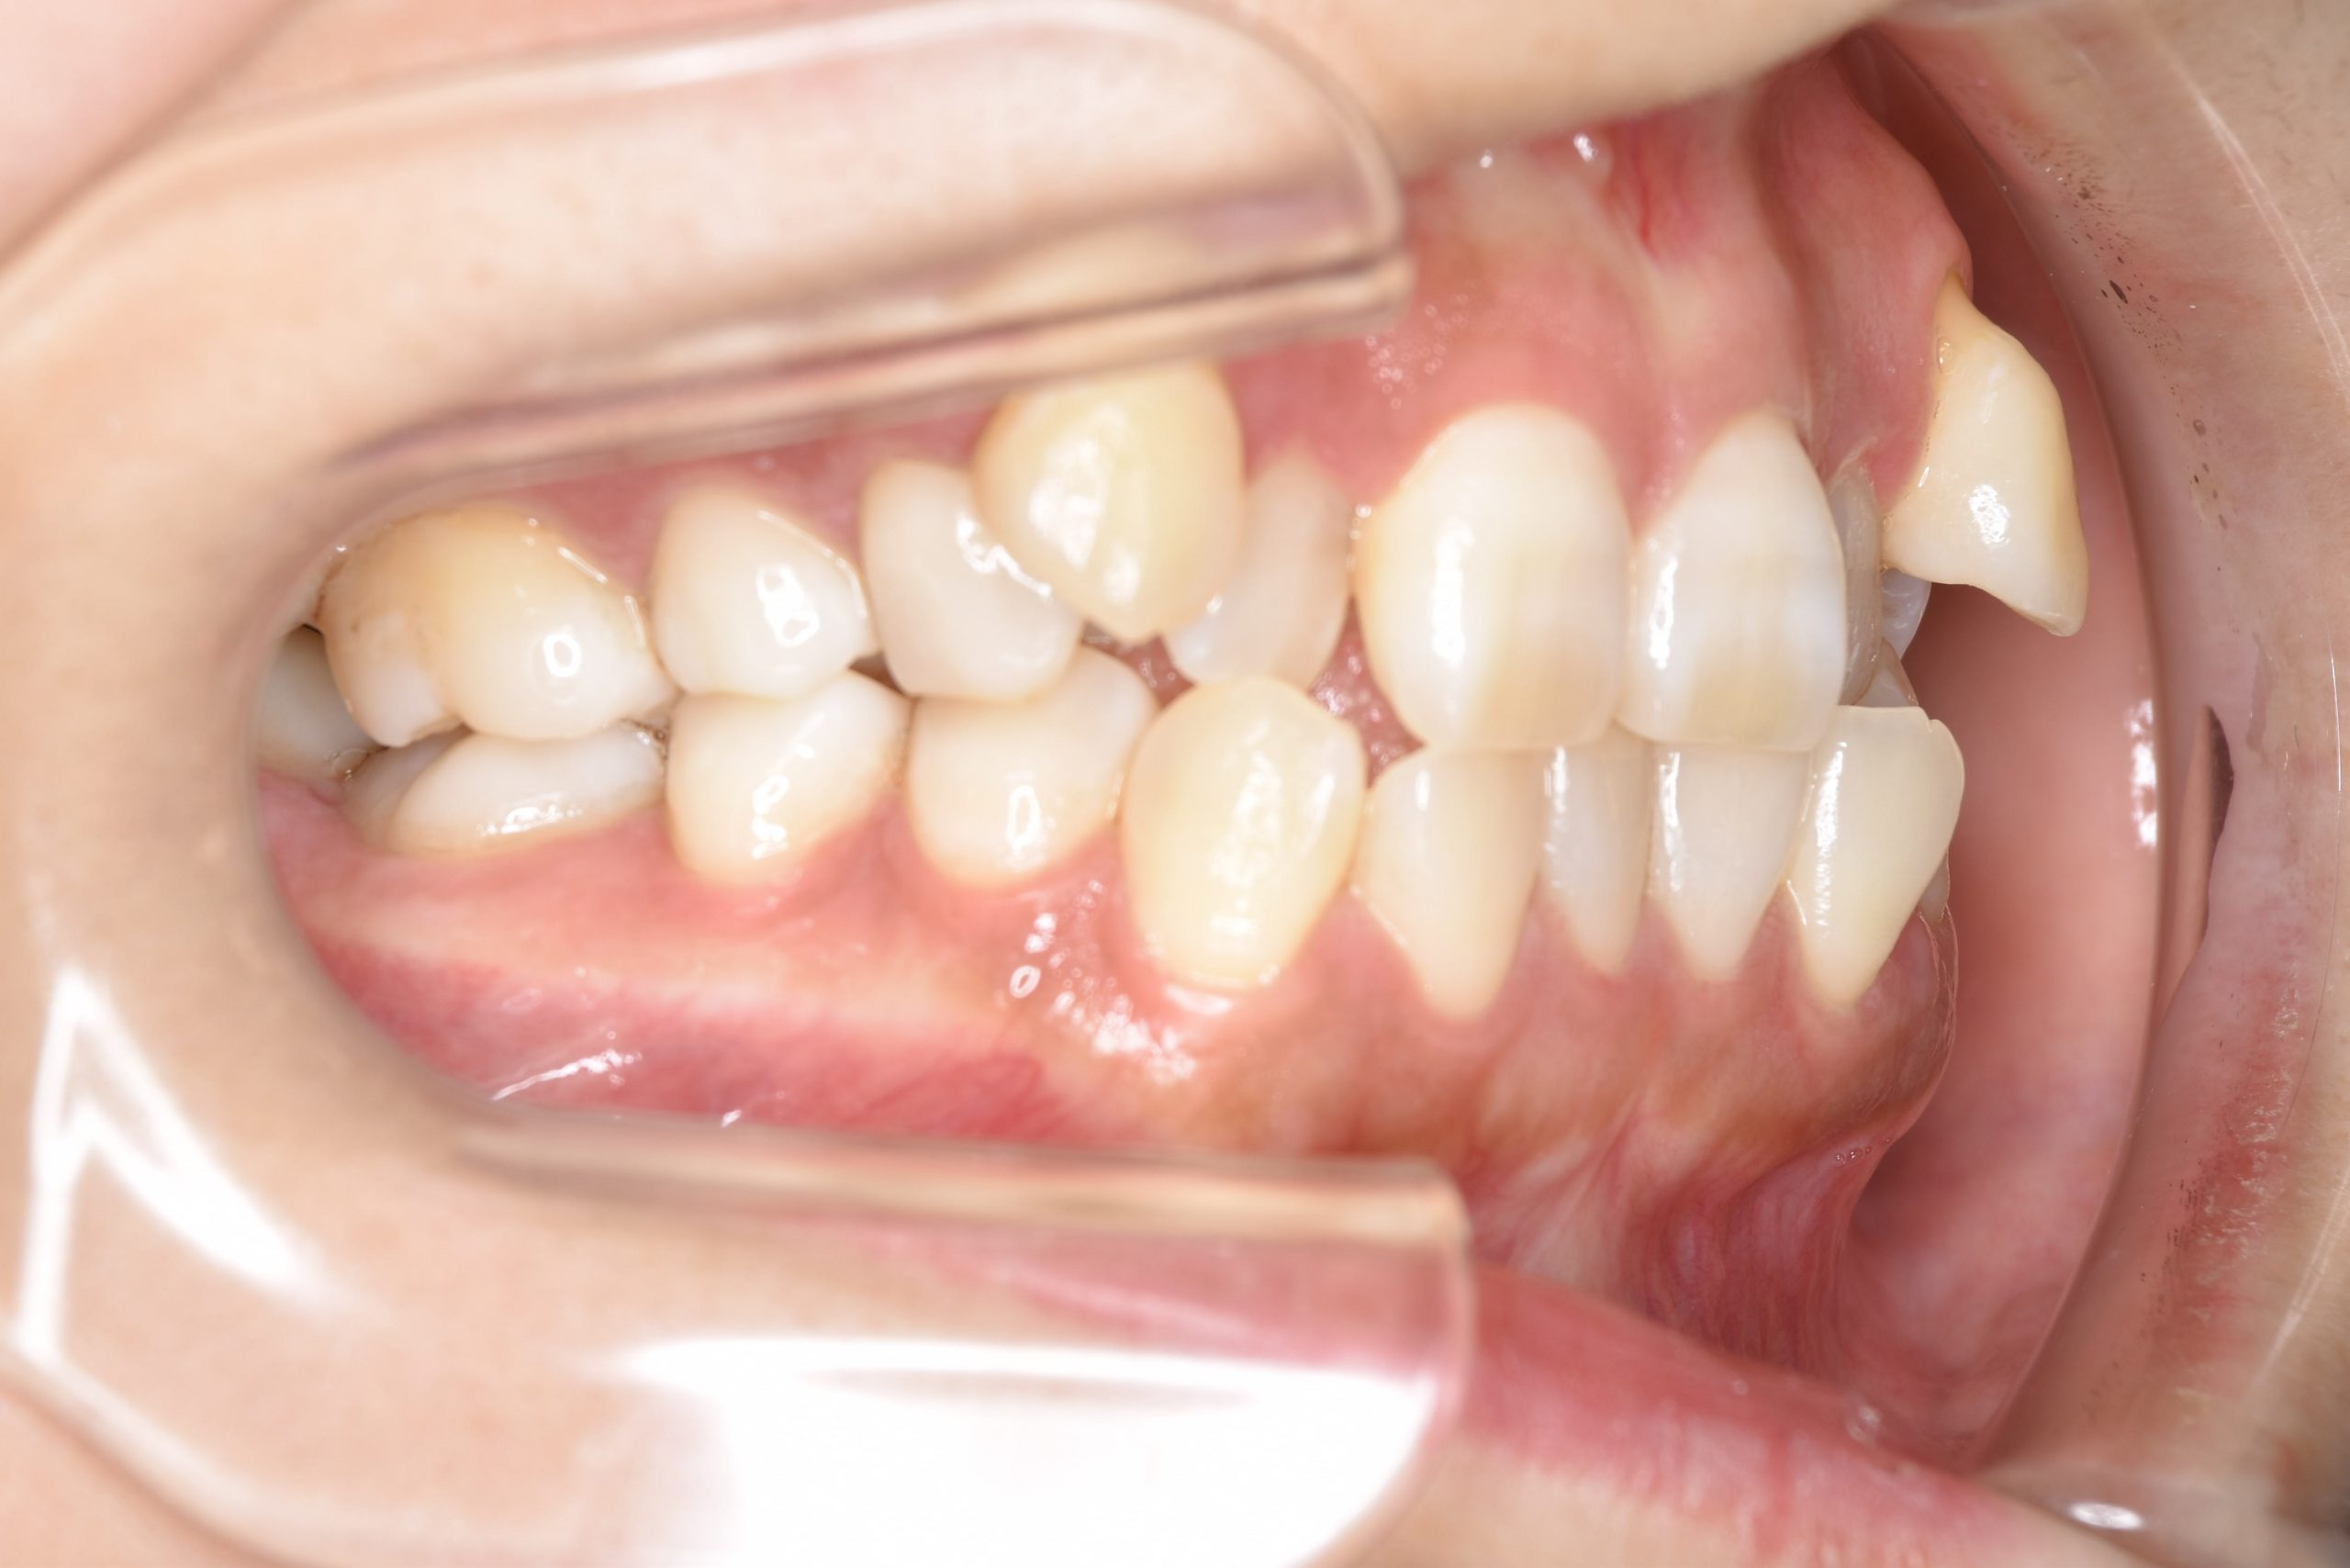

アフター

全顎ワイヤー矯正 症例_141

主訴 八重歯|上下センターがずれている

施術内容 成人矯正1期治療

治癒期間 4年10ヶ月間

費用 1,106,560円(税込)